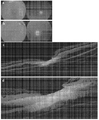

- 238000012014 optical coherence tomography Methods 0.000 description 20

- 238000002571 electroretinography Methods 0.000 description 23